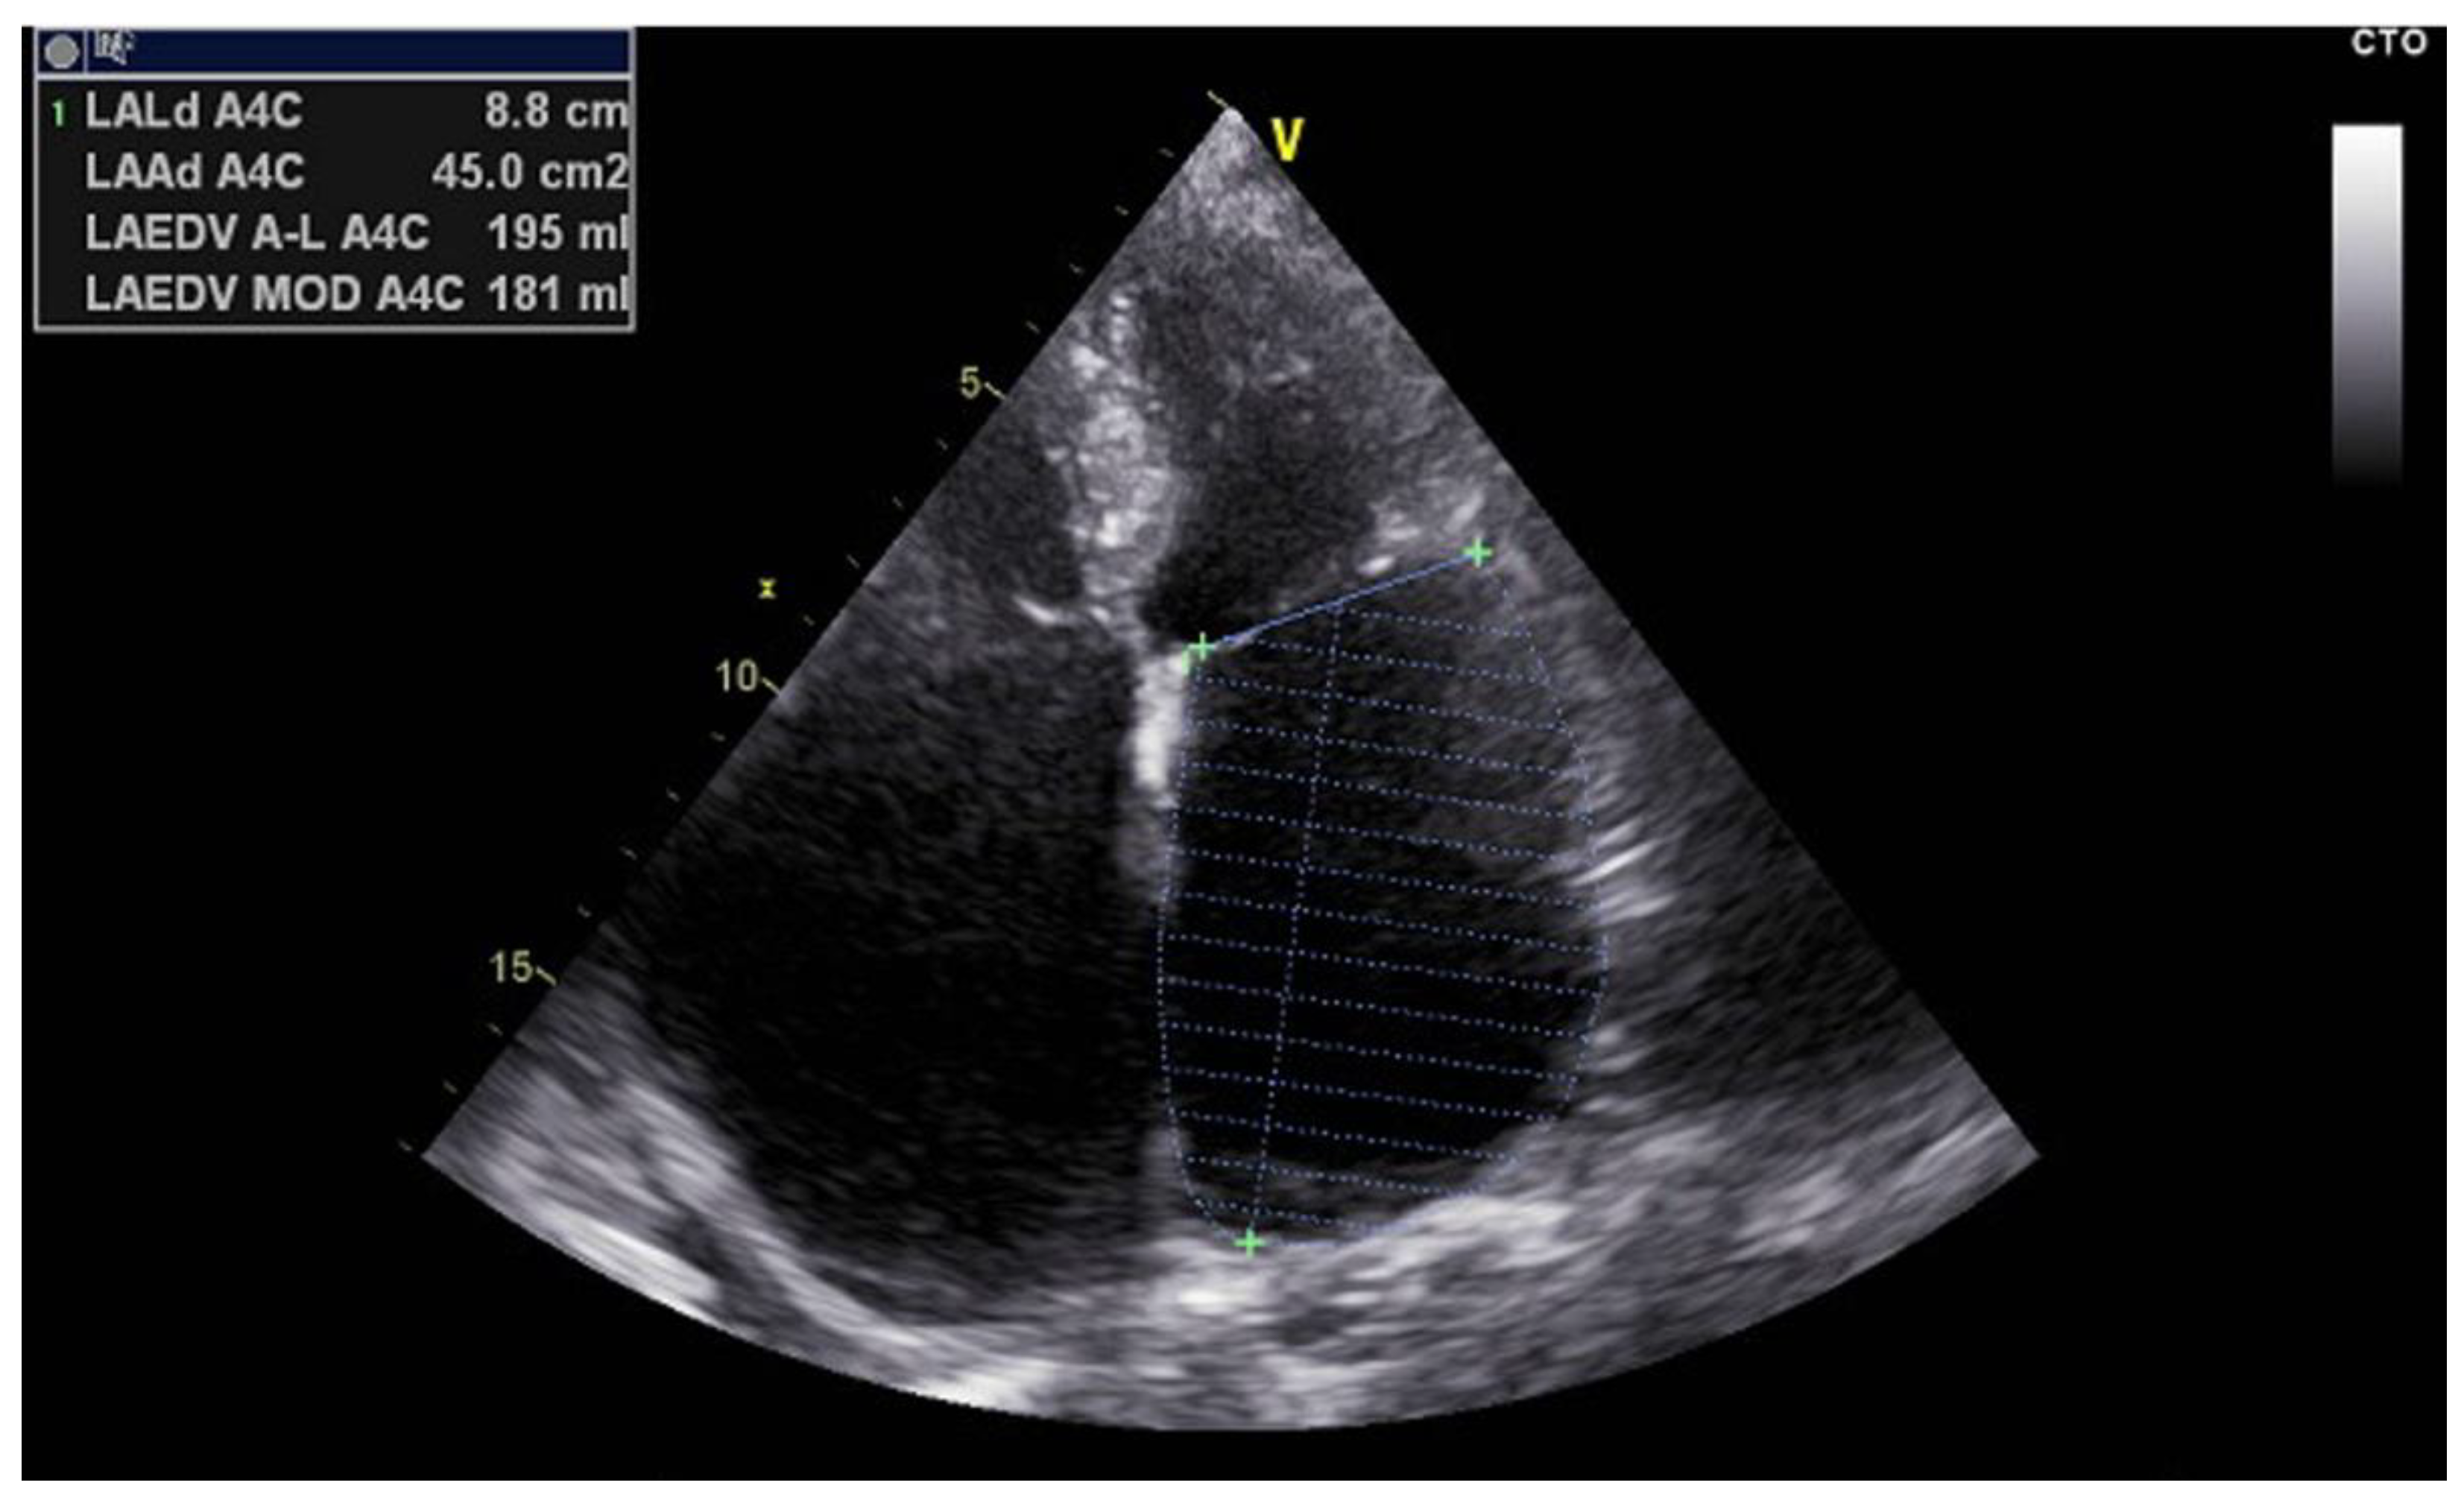

- Left Atrial Volume Index (LAVI): LAVI quantifies the size of the left atrium indexed to body surface area and is measured using the biplane method of disks (modified Simpson’s rule) from apical four- and two-chamber views [25] (Figure 3). Normal LAVI is below 34 mL/m², with values between 34 and 48 mL/m² representing mild to moderate enlargement, and values above 48 mL/m² indicating severe dilation. Increased LAVI reflects chronic pressure or volume overload, often linked to diastolic dysfunction or longstanding atrial fibrillation [26]. It is a robust predictor of adverse cardiovascular events and procedural failure in AF ablation.